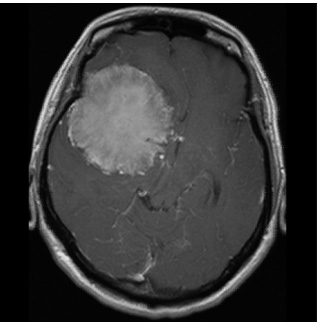

症例3は42歳女性。意識消失にて発症。CT、MRIにて内頸動脈、中大脳動脈を巻き込む大型の前床突起部起源の髄膜腫を認める。

中大脳動脈の血流が低く、血管損傷を来す可能性もあるので、浅側頭動脈-中大脳動脈バイパスをおいた後に腫瘍内より血管を掘り起こすように摘出を行った。

細い脳深部に至る血管も保護して摘出した。術後四肢麻痺等なく回復。

術前画像:内頸動脈などの血管を巻き込み狭窄する(反対側と比較)腫瘍をみとめ周囲に脳の腫れを認める。

術後画像:腫瘍はほぼ摘出され、脳梗塞等の合併症は認めない。